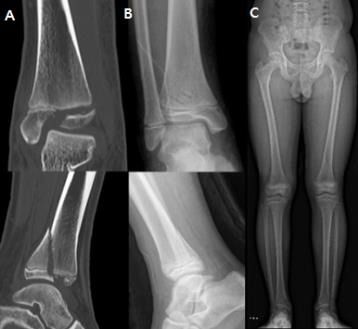

▲ 사진제공=분당서울대학교병원

분당서울대학교병원 정형외과 성기혁 교수 연구팀이 소아의 발목 성장판 골절 치료에 사용하는 생체흡수성 나사와 금속 나사를 이용한 수술 결과를 비교한 연구 결과를 발표했다.

발목 성장판 골절은 뼈의 성장에 중요한 역할을 하는 성장판을 포함하는 발목 부위가 손상된 것을 말하며, 10세 전후의 소아에게 흔하게 발생한다. 골절 부위의 뼛조각이 정상 위치에서 크게 어긋날 경우, 제대로 붙지 않거나 성장판이 손상돼 다리 변형이나 길이 차이가 생길 위험이 있어 수술적 치료가 필수적이다.

골절 부위를 고정하기 위해서는 나사가 사용되는데, 이 때 금속 나사를 사용하는 경우 나사를 제거하기 위한 2차 수술이 필요해 환자와 가족에게 부담을 야기할 수 있다. 이에, 최근에는 시간이 지나면 몸속에서 자연적으로 분해·흡수돼 추가 수술이 필요 없는 생체흡수성 나사가 효과적인 대안으로 주목받고 있다.

연구팀은 발목 성장판 골절로 수술을 받은 15세 이하의 환아 67명을 대상으로, 금속 나사(40명)와 생체흡수성 나사(27명)를 이용한 수술 결과를 비교했다. 그 결과, 두 군 모두에서 성장판 손상 비율, 수술 시간, 수술 후 발목 기능이 우수했으며, 수술 후 감염, 상처 등 합병증 또한 없어 유의미한 차이 없이 동등한 치료 결과를 보였다.

하지만 입원 기간에 차이가 있었는데, 생체흡수성 나사를 이용한 수술을 받은 환자군의 평균 입원 기간은 2.6일로, 금속 나사를 이용한 수술을 받은 환자군(5.2일)보다 절반가량 짧아 시간적 부담이 적은 것으로 나타났다. 특히, 연구팀은 생체흡수성 나사가 나사 제거를 위한 추가 수술이 필요하지 않기 때문에 전신 마취로 인한 위험을 피할 수 있다는 점에서 소아 환자에게 보다 안전한 대안으로서 활용될 수 있다고 제시했다.